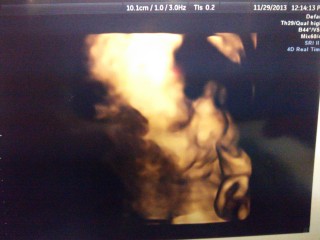

30w1d! BaByくん、 重さ1367g前回より+265g大きくなってました。 先生からゎ平均的だから大丈夫!と言われました。 エコー写真ゎ途中で寝てしまったBaByくんです。 最近ゎジブリのオルゴールのBGMを お腹の↑で流してあげたら、めっちゃ動いてくれます!

里帰りで初めての4Dエコーでした♪ 5ヶ月の時に男の子と言われ、おまたを隠していて見せてくれなかったのですが、しっかり見せてくれて、まさかの女の子でした!!嬉しいです♪ 1380グラムとのことです!!

今まで、ずっと下を向いていたので4Dエコーが撮れなかったんですが、やっと、回転してくれて、上向いてくれました!